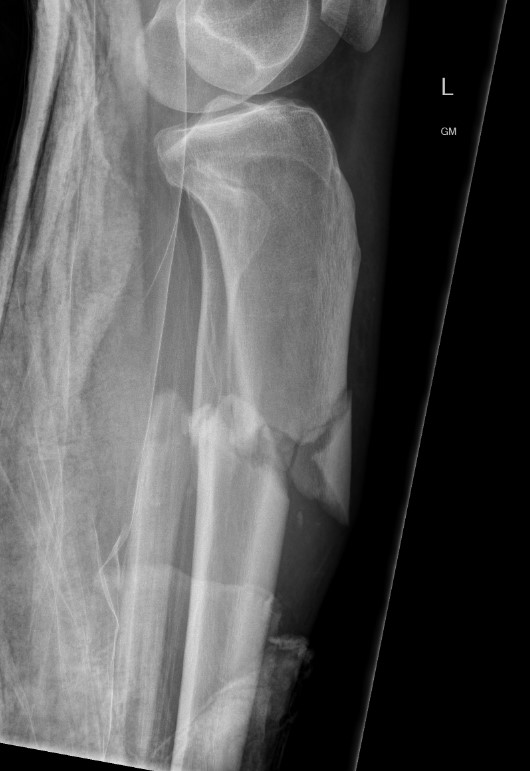

Characteristic valgus deformity with extension of the proximal fragment

Issue

High incidence malunion

- coronal plane valgus

- saggital plane flexion / procurvatum

- posterior translation of distal segment